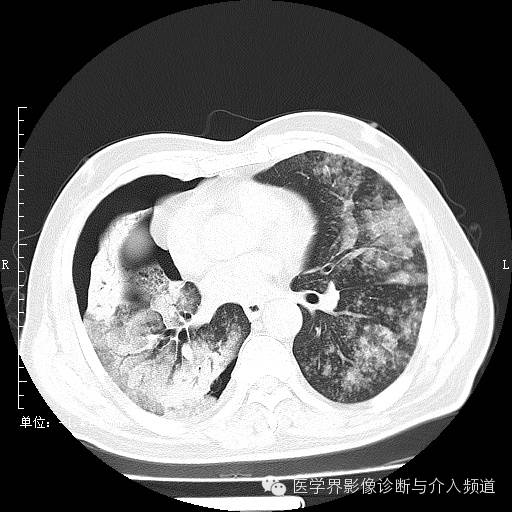

二次复查

二次复查:双肺多发实变、磨玻璃结构及粟粒结节,较前病变范围明显增大右侧并发气胸。